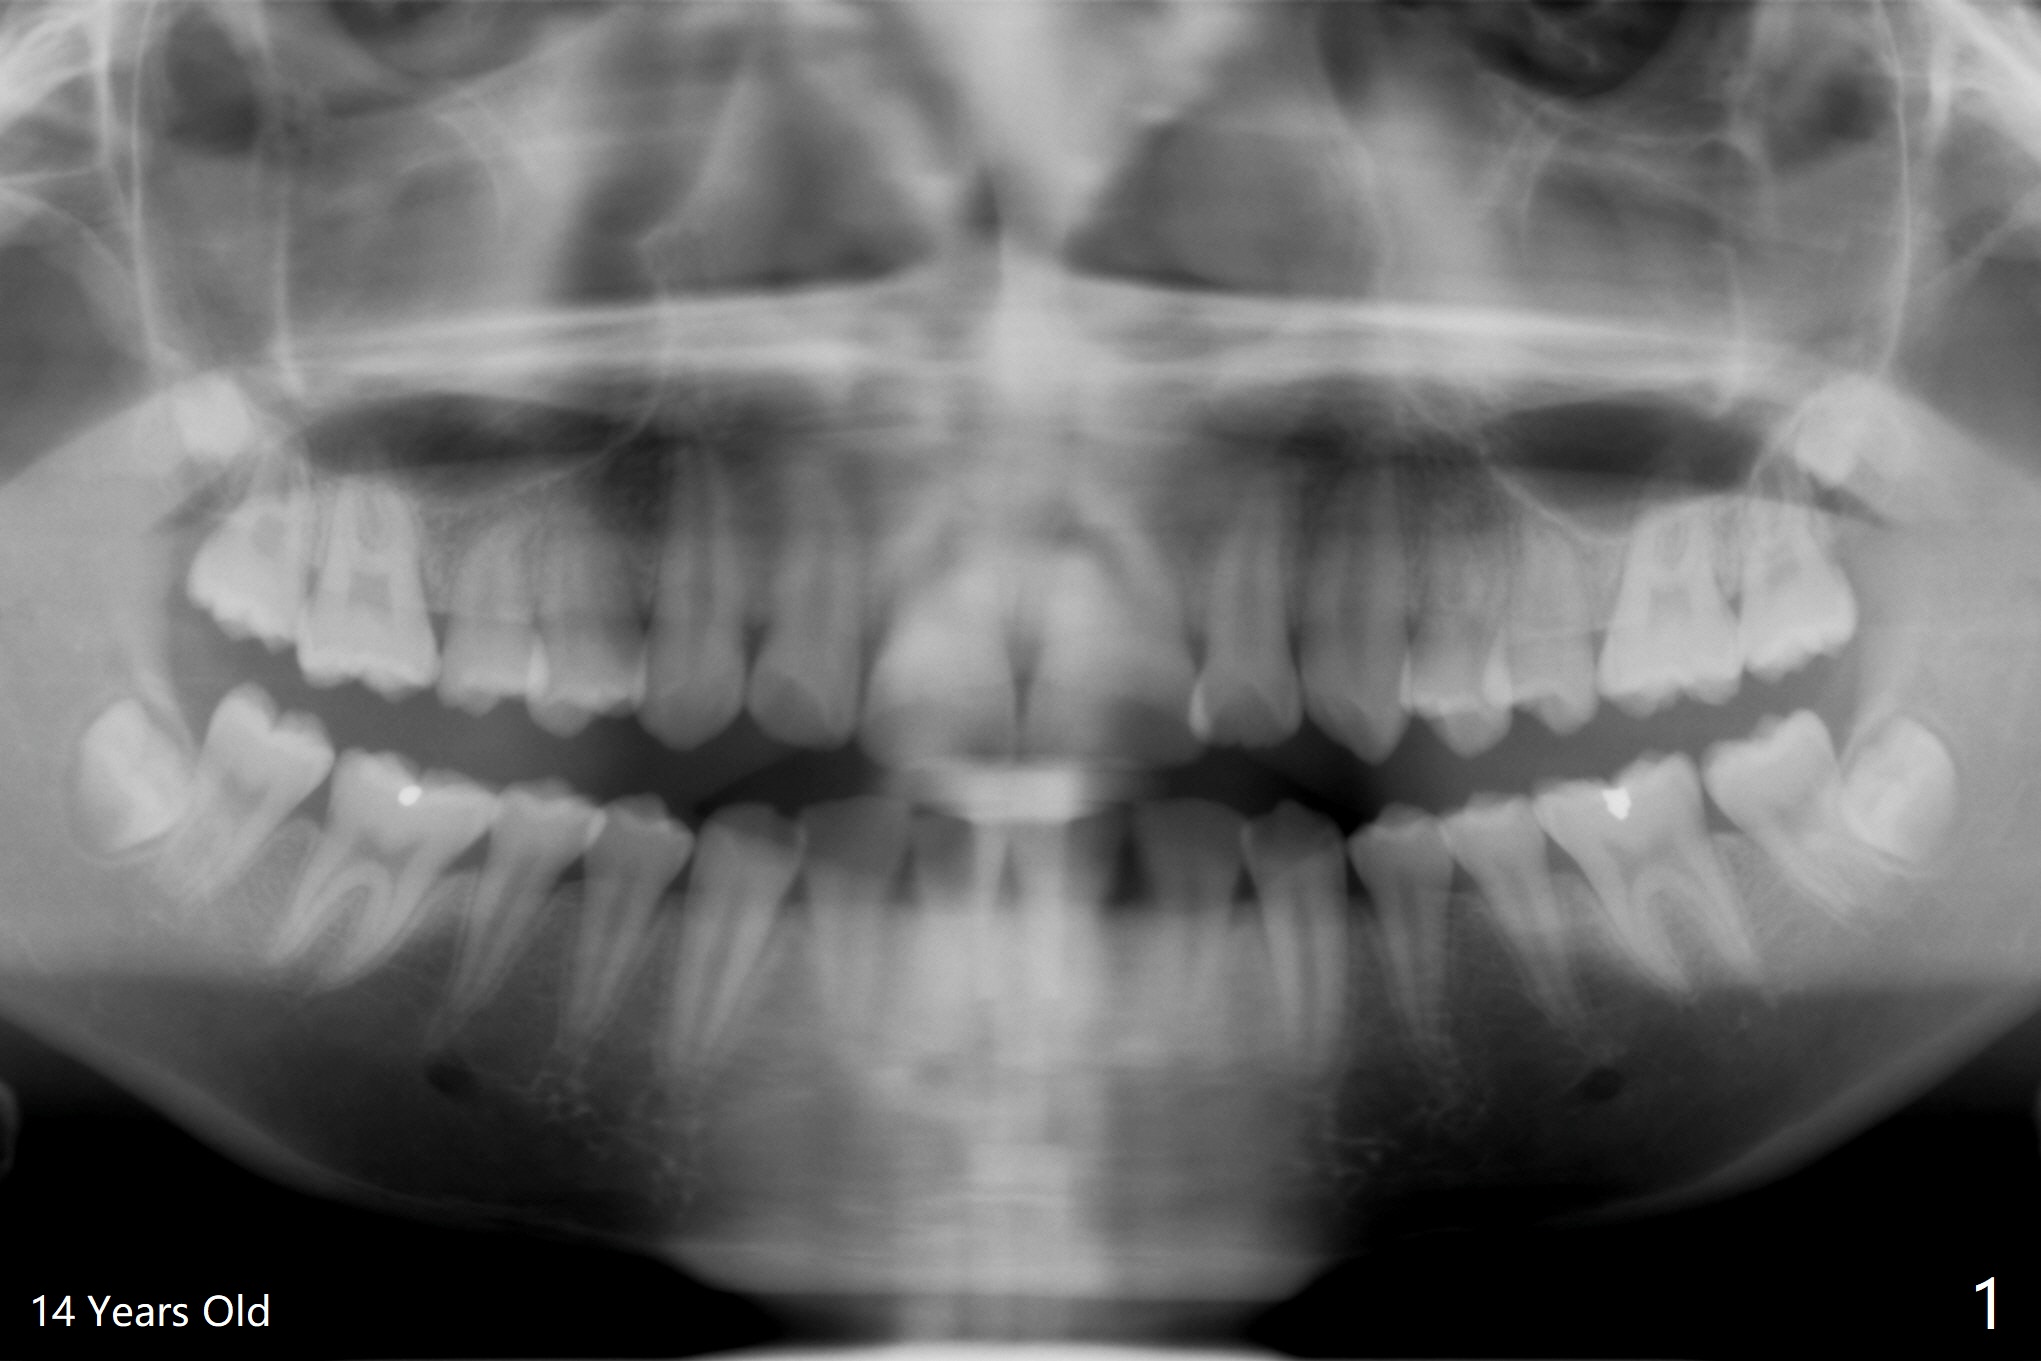

A 25-year-old woman, under our care for the last 11 years (Fig.1-6), returns for #1 and 32 extraction (1 year after #16 and 17 extraction (Osteogen plug)). Preop PA shows that a portion of the lower impacted tooth may be located buccal to the tooth #31 (Fig.4 black dashed line). An accessory incision is moved from distobuccal to midbuccal (Fig.7 arrowheads) to reduce postop loss of bone graft (Fig.8 B) from the incision. In fact the incision should be further moved to mesiobuccal (Fig.9 red line) if buccal impaction is suspected (curved black line). The buccal impaction of #32 of her father is more severe.